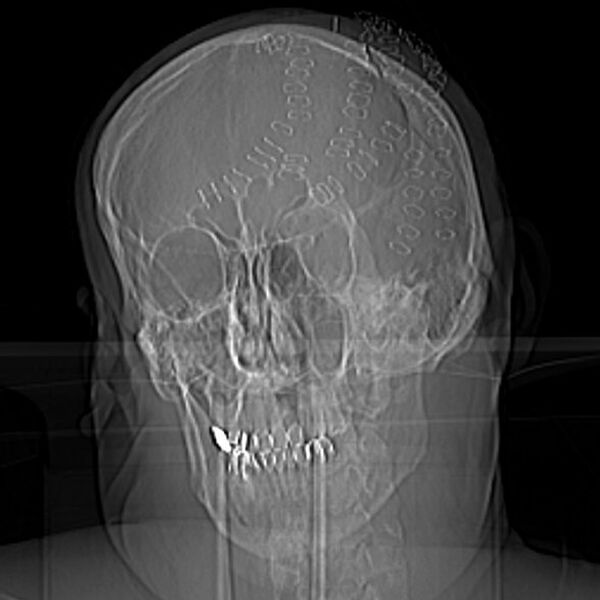

Во Владивостоке врачи Тысячекоечной больницы спасли 50-летнего мужчину с раздробленным черепом в результате удара топором. Об этом рассказали в пресс-службе медицинского учреждения.

Пациент получил бытовую травму на острове Попова, откуда его экстренно эвакуировали на катере. Несмотря на сложность эвакуации, через три часа после инцидента, нейрохирурги приступили к операции. Мужчине диагностировали рубленные раны головы, множественные оскольчатые и вдавленные переломы теменных костей, травматическое субарахноидальное кровоизлияние, ушиб головного мозга. Медики отметили, что к моменту его поступления в стационар требовалась срочная операция.

«Из-за обширной потери крови он впал в геморрагический шок, что угрожало его жизни. Врач-нейрохирург Никита Барышников внимательно изучил повреждения и начал обработку ран, удаление вдавленных фрагментов костей черепа, а также остановку кровотечения из поврежденных сосудов», — рассказали в пресс-службе.

Медики несколько часов собирали мужчине череп по частям, операция завершилась успешно.